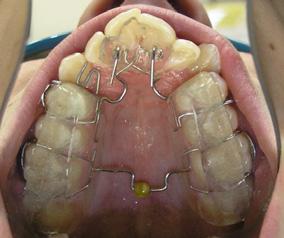

Posterior TADs were removed, when interdigitations of the maxillary cuspids and first bicuspids was achieved, we initiated the protraction of the first molars. Commercial laboratory soldered buccal power arms to the orthodontic bands on #16(3) and #26(14). These power arms allowed us to apply the force close to the center of resistance of the first molars. The TADs inserted distally to maxillary second incisors previously, served two purposes: intrusion of the anterior sextant and protraction of the maxillary first molars. The applied force was delivered with an Elastomeric chain. To prevent excoriation of the attached gingiva a .018 x .025 hand bent tissue shield was bonded to the buccal surface of #13(6) (Figure 9-A, B, C, D).

The side effect of protraction of the first molars is a mesiolingual moment (rotation). To neutralize this, the force must be applied, from the palatal aspect with the Power thread or the Elastomeric chain. The Power thread is attached to the lingual cleat of the molar bands, and it is stretched to the maximum, then tied to the arch wire between the cuspids and lateral incisors. A 3/16” – 4.5 oz Class III elastic was placed on the right side and a ¼”4.5 oz triangular elastic was placed on the left side to ameliorate the interdigitation (Figure 10-A, B, C).

FIG. oral mucosa FIG. 9C: Tissue guard, right lateral view FIG. 9D: Protraction of the first molar, left lateral view FIG. 10A: Lingual intra – Power thread, occlusal view FIG. 10B: Class II elastic, right lateral view FIG. 10C: Triangular elastic, left lateral view FIG. FIG. FIG. 12A: “W” with tail, right lateral view FIG. 12B: “W” with tail, left lateral view